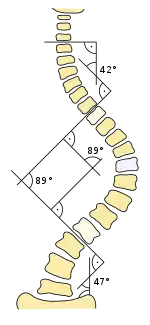

Es habitual que cuando se sospecha de escoliosis, se tomen radiografías del tórax en planos anteroposterior/coronal, y lateral/sagital, para evaluar las curvas de la escoliosis, además de las curvas normales de cifosis y lordosis, ya que estas también pueden estar afectadas en personas con escoliosis. Los rayos X de la columna en un paciente de pie, son el método estándar para evaluar la severidad y progresión de la escoliosis, y si es de naturaleza congénita o idiopática. En individuos en crecimiento, las radiografías seriales se obtienen en intervalos de 3-12 meses para seguir la progresión de la curvatura, y en algunos casos, se necesita además de resonancia magnética para examinar la médula espinal.

El método estándar para evaluar cuantitativamente la curvatura es la medida del ángulo de Cobb, el cual es el ángulo entre dos líneas, dibujado perpendicularmente a la placa terminal superior de la vértebra más superior involucrada y la placa terminal inferior de la vértebra más inferior afectada. Para los pacientes que tienen dos curvas, los ángulos de Cobb se siguen para ambas curvas. En algunos pacientes, se obtienen rayos X con inclinación lateral para evaluar la flexibilidad de las curvas o las curvas primaria y de compensación.